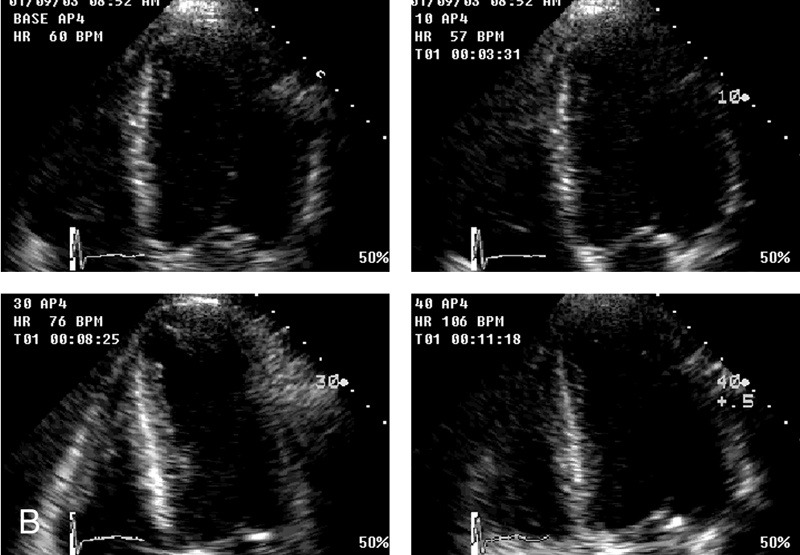

فحوصات تشخيصية لبعض امراض القلب والشرايين التاجية